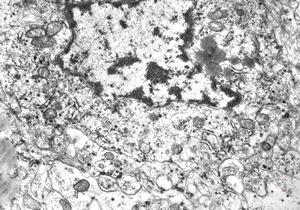

F,69y. | regenerating muscle cell

F,56y. | regenerating muscle cell